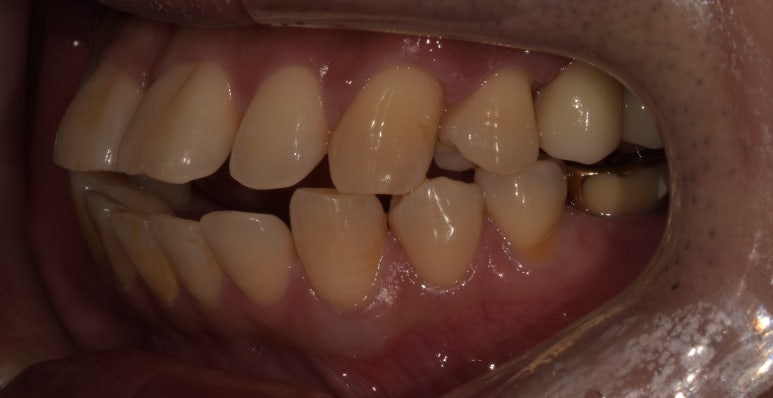

실제 구내 사진을 함께 보실까요?

임플란트 수술 전후

(전) 2022-04-28 (후) 2023-04-06

사진을 보시면 특히 #26 같은 경우는 육안으로 보기에도 치아 뿌리가 노출되는 등

임플란트가 시급한 상태였는데, 치료 후에는 제자리에 치아가 잘 자리잡고 있는 것을 확인할 수 있습니다.